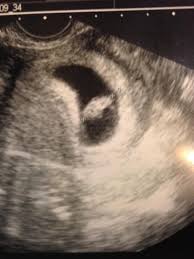

Also during that pregnancy Tiffany was diagnosed with a form of uterine cancer. Also during that pregnancy Tiffany was diagnosed with a form of uterine cancer. Adam called the next day and said my blood test came back that I was almost 8 weeks pregnant and since I just had Raygen she was immediately concerned and scheduled me an ultrasound.